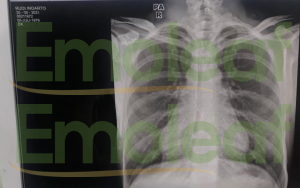

20 September 2022 Saya cek Rontgen kembali. Hasil rontgen menunjukan bahwa Paru – Paru sudah bersih dari kanker dan tidak ada cairan sehingga tidak diperlukan operasi.

20 September 2022, Hasil Rontgen Paru – Paru bersih

Alhamdulillah bisa pulih dan menghemat biaya, saya juga bisa bekerja normal tanpa ada keluhan.